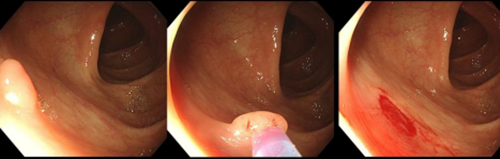

其中活检钳钳除术是指通过内镜的活检孔道,护士会协助医生将活检钳进入到肠腔内,将息肉完整钳除(图1)。而冷圈套息肉切除术,是通过活检孔道送入圈套器后完整的套取息肉,逐渐收紧圈套器后将息肉切除(图2)。

图1 活检钳除